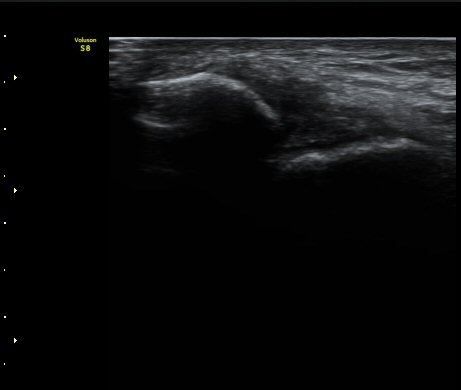

Àüºñ°ñ°æ°ñÀδë Á¾´Ü¸é°Ë»ç¿¡¼­ ƯÀÌ ¼Ò°ßÀ» º¸ÀÌÁö ¾Ê´Â´Ù(±×¸² 2).

±×¸²2) Àüºñ°ñ°æ°ñÀδë Á¾´Ü¸é°Ë»ç±Û